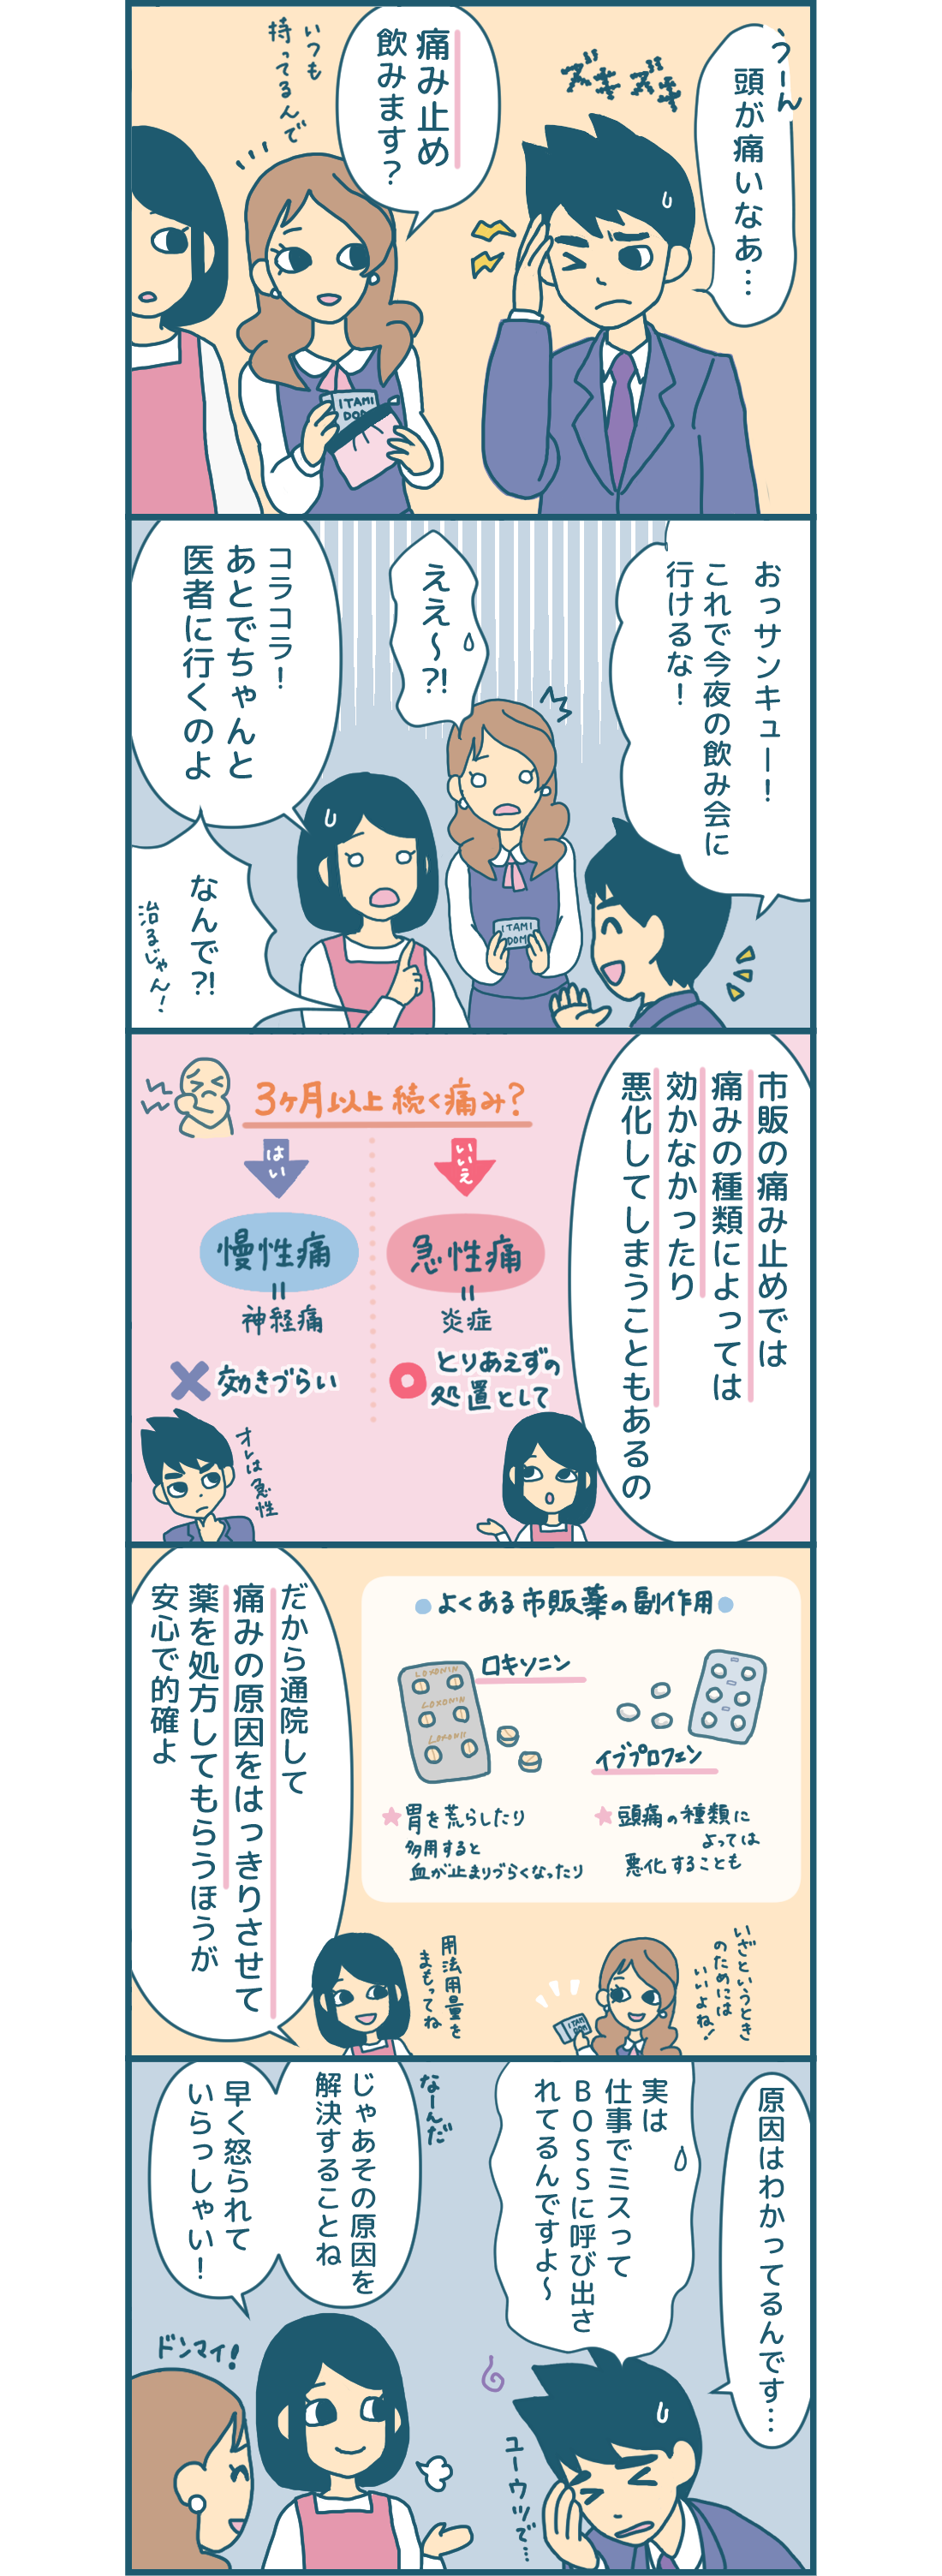

薬物乱用頭痛 タイプ別の頭痛 頭痛 生理痛 肩こり痛など さまざまな痛みに ロキソニンsシリーズ 第一三共ヘルスケア

薬物乱用頭痛 タイプ別の頭痛 頭痛 生理痛 肩こり痛など さまざまな痛みに ロキソニンsシリーズ 第一三共ヘルスケア

漫画付き ロキソニン や イブプロフェン は どんな痛みでも服用して大丈夫

薬物乱用頭痛 タイプ別の頭痛 頭痛 生理痛 肩こり痛など さまざまな痛みに ロキソニンsシリーズ 第一三共ヘルスケア

薬物乱用頭痛 タイプ別の頭痛 頭痛 生理痛 肩こり痛など さまざまな痛みに ロキソニンsシリーズ 第一三共ヘルスケア